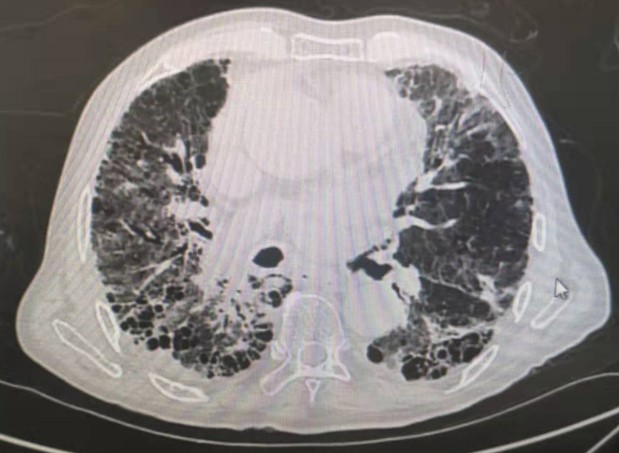

第三类,肺间质性疾病。肺间质,可以简单的理解为肺泡与肺泡之间的间隔,肺脏内的血管、淋巴管都在肺间质内穿行。当各种原因导致间质增厚时,肺泡膨胀受限,会引起肺脏密度增高。比较常见的是间质性肺炎,还包括一些肺部血管炎性疾病和淋巴管疾病。

双肺间质性肺炎,表现为不均匀的磨玻璃样改变和肺间质增厚